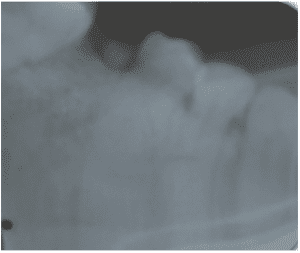

A 49-year-old female patient attended the prosthesis clinic at Nilton Lins University, mentioning dissatisfaction with her total obturator prosthesis, because she had a “broken front tooth” and the prosthesis was “falling”, emphasizing the desire to maintain the shape of the same. In the anamnesis reported that previously in 2012 he was diagnosed with mucoepidermoid carcinoma of intermediate degree in the palate (Appendix 1) and in 2013 after performing surgical removal and performing new tests, who did not indicate the presence of malignancy (Appendix 2), was attested as cured, besides being hypertensive and using the drugs losartan potassium 50 mg twice daily and levanlodipine besidate 2.5 mg once a day. No alterations were observed on extraoral clinical examination. In the intraoral clinical examination, there was absence of the upper arch teeth, bucosinusal communication and partial maxillary edge and in the lower region only the presence of teeth 31, 32, 33, 41, 42, 43, 44 and 45 (figures 1 and 2).

Figure 1: Surgical defect of the upper arch.